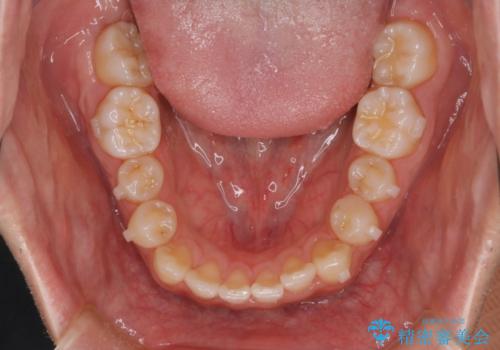

- 前歯のがたつきを主訴に来院されました。初診時、右上2番の口蓋側転位と右下7番の舌側傾斜が認められました。

インビザラインにてIPRと歯列弓拡大を行い、ゴム掛けで噛み合わせを改善する治療計画を立てました。

マウスピースの使用時間が短いため、シュミレーション通り進むか不安でしたが

治療期間1年で、主訴である前歯のがたつきを改善出来、

奥歯の噛み合わせも良くなりました。